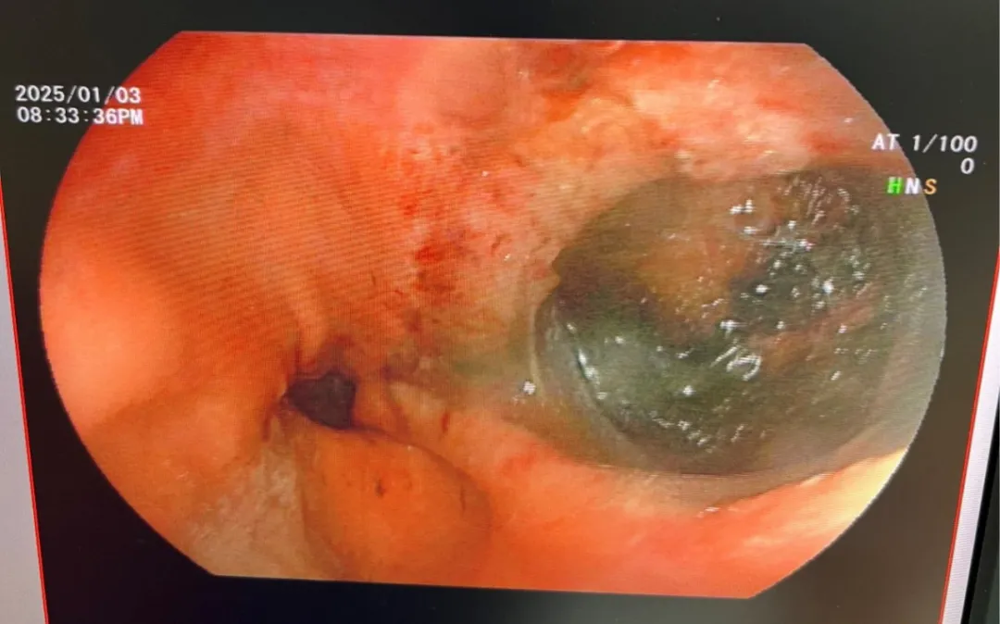

患者,盧某,67歲,因突發劍突下疼痛1天來院就診,呈鑽(zuàn)心樣劇烈疼痛,伴有惡心(xīn)、嘔吐,胸部CT示後(hòu)縱膈食管周圍積氣,提示食管穿(chuān)孔,立即急診行胃鏡檢查,胃鏡(jìng)下見食道下段右後壁可見一個巨大裂口,周圍少量血痂。入院診斷為自發性食管破裂,因患者發熱伴縱膈有膿腫形成,病情危(wēi)重,立即啟動危重(chóng)患者搶救流程,並邀請(qǐng)上級專家會診,專家建(jiàn)議立即手術治療,在專家的幫(bāng)助(zhù)下急診為患(huàn)者行手術(食道自(zì)發性(xìng)破(pò)裂修補術(shù)+縱膈膿腫清(qīng)除+T管引流+縱(zòng)膈引流術+小腸(cháng)營養管植(zhí)入術)。患者(zhě)已經痊愈出院2個月(yuè),恢複良好(hǎo)。